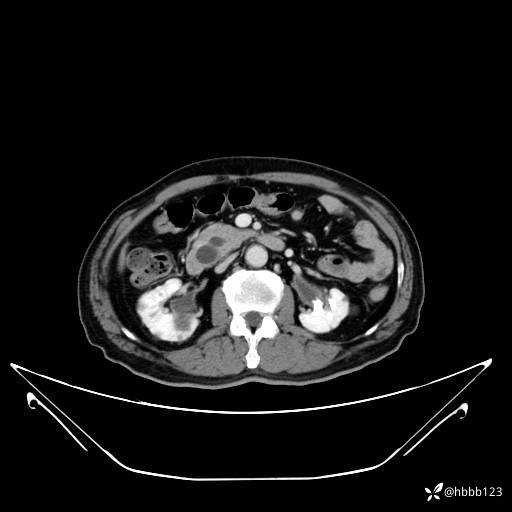

延迟期: